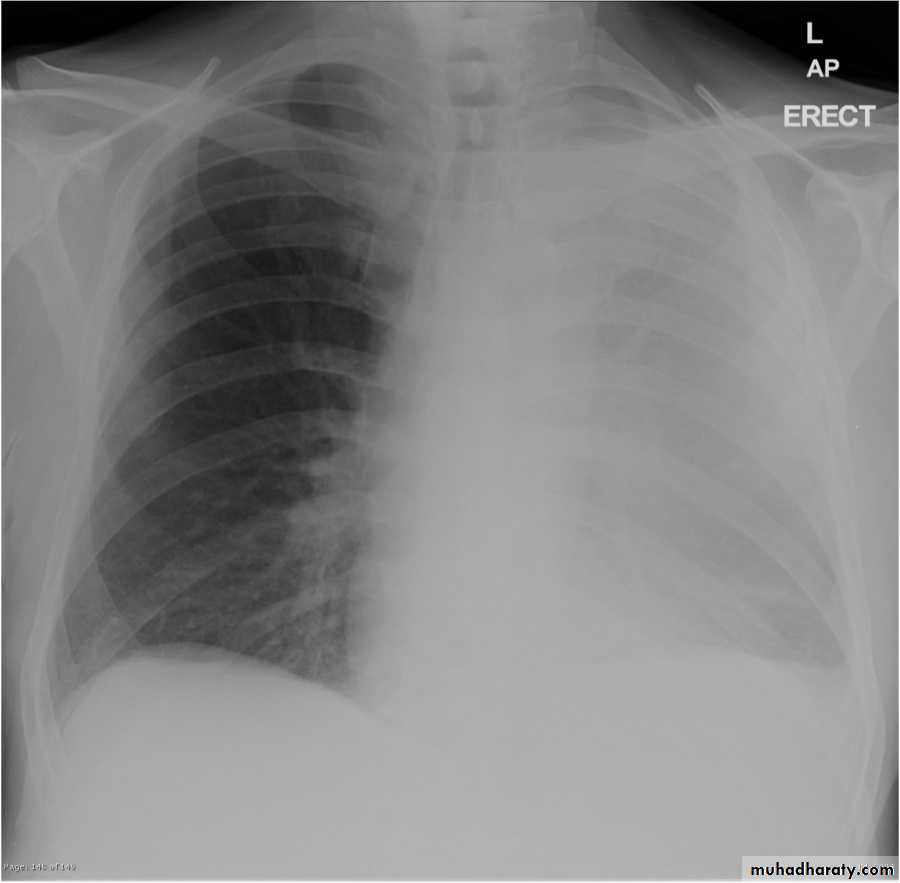

Pleural effusion

50.pleural effusion

51.pleural effusion .